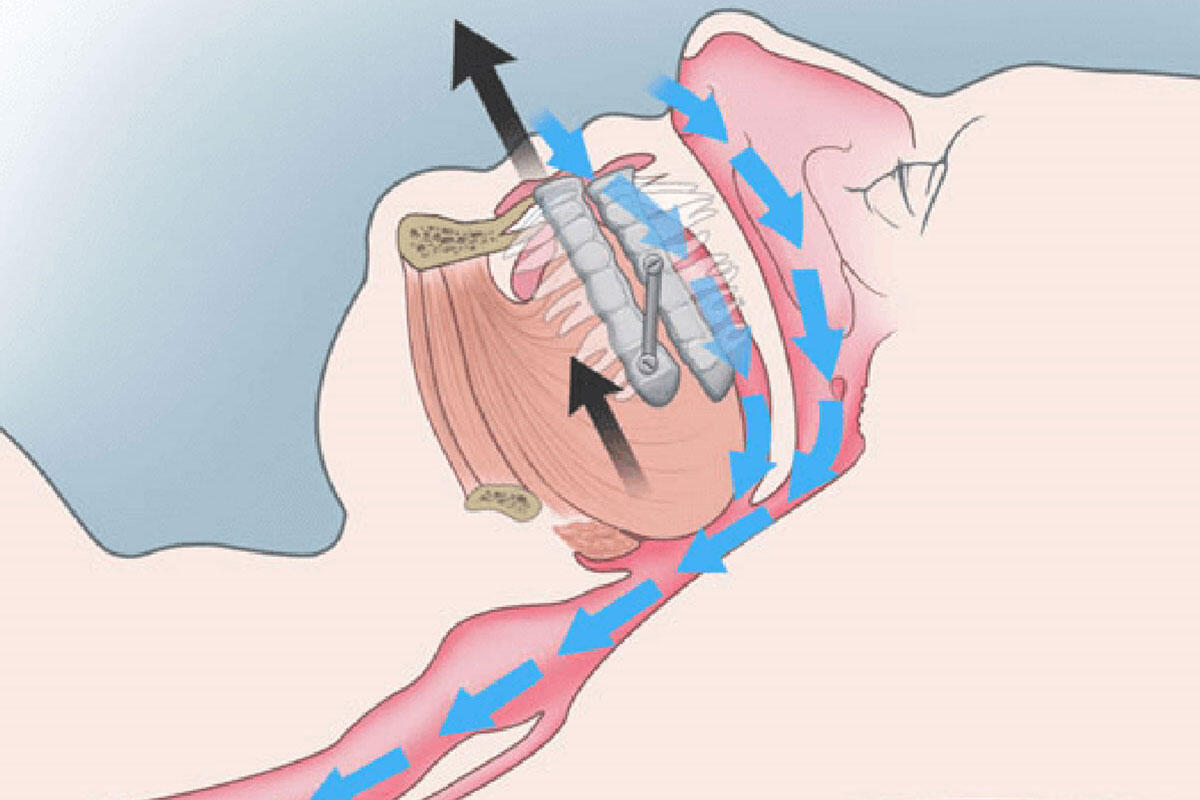

L’odontoiatra rappresenta sempre più una figura chiave in questa patologia sia nel sospetto diagnostico, sia nella gestione e nel monitoraggio della terapia con dispositivi da tenere in bocca la notte che favoriscono l’avanzamento mandibolare liberando il passaggio dell’aria nelle vie aeree superiori.

Esistono svariate tipologie di propulsori mandibolari (MAD) tutti volti ad avanzare mandibola e lingua: l’odontoiatra esperto nei disturbi del sonno saprà scegliere il dispositivo più idoneo tenendo conto dei fattori legati allo specifico paziente.